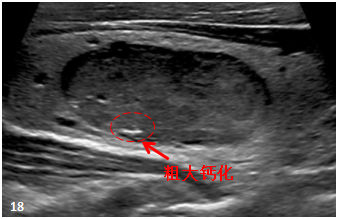

“粗钙化”是直径>2毫米的强回声斑块,其后面有声影,多发生在纤维化或组织退变的区域(图18)。 良性和恶性结节均可见。 如果它们与微钙化同时出现,恶性肿瘤的风险就会增加。

![图片[10]-一份甲状腺超声报告到手,从哪看起?-首码网-网上创业赚钱首码项目发布推广平台](https://mmbiz.qpic.cn/mmbiz_png/XsibUvKtQsKyibvUiaI0WiaTnGBzic2SSvxXQohJZqzcsYvvpKhcA3BalX5TNV1uAdvIKFCKgyE5eqsZcPH3LrWXeVg/640?wx_fmt.png)

资料来源:2015 ACR 白皮书甲状腺超声报告专用术语